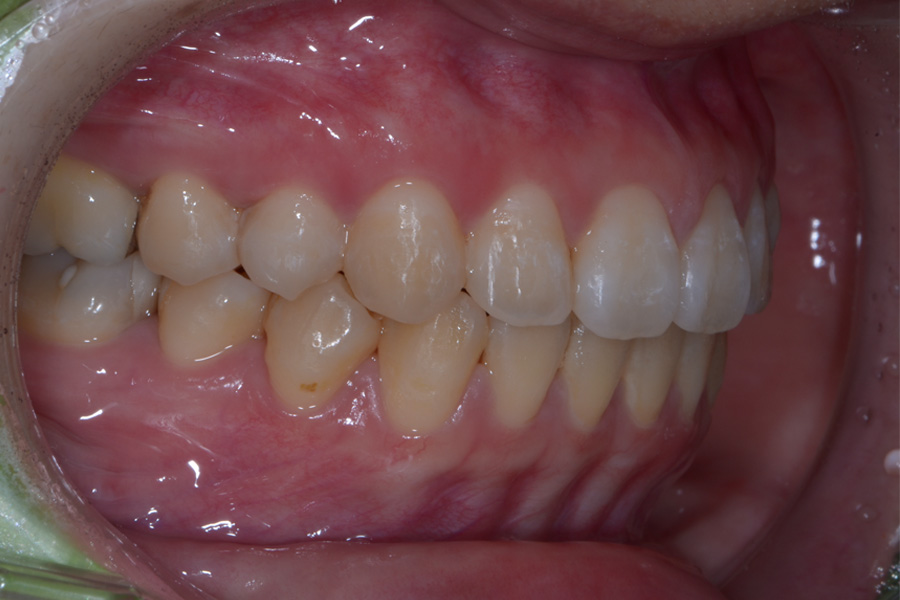

治療後

主訴 出っ歯とすきっ歯を治したい

期間 5か月

費用 20万円(別途調整料)

治療内容 上顎ラビアル矯正(表側矯正)